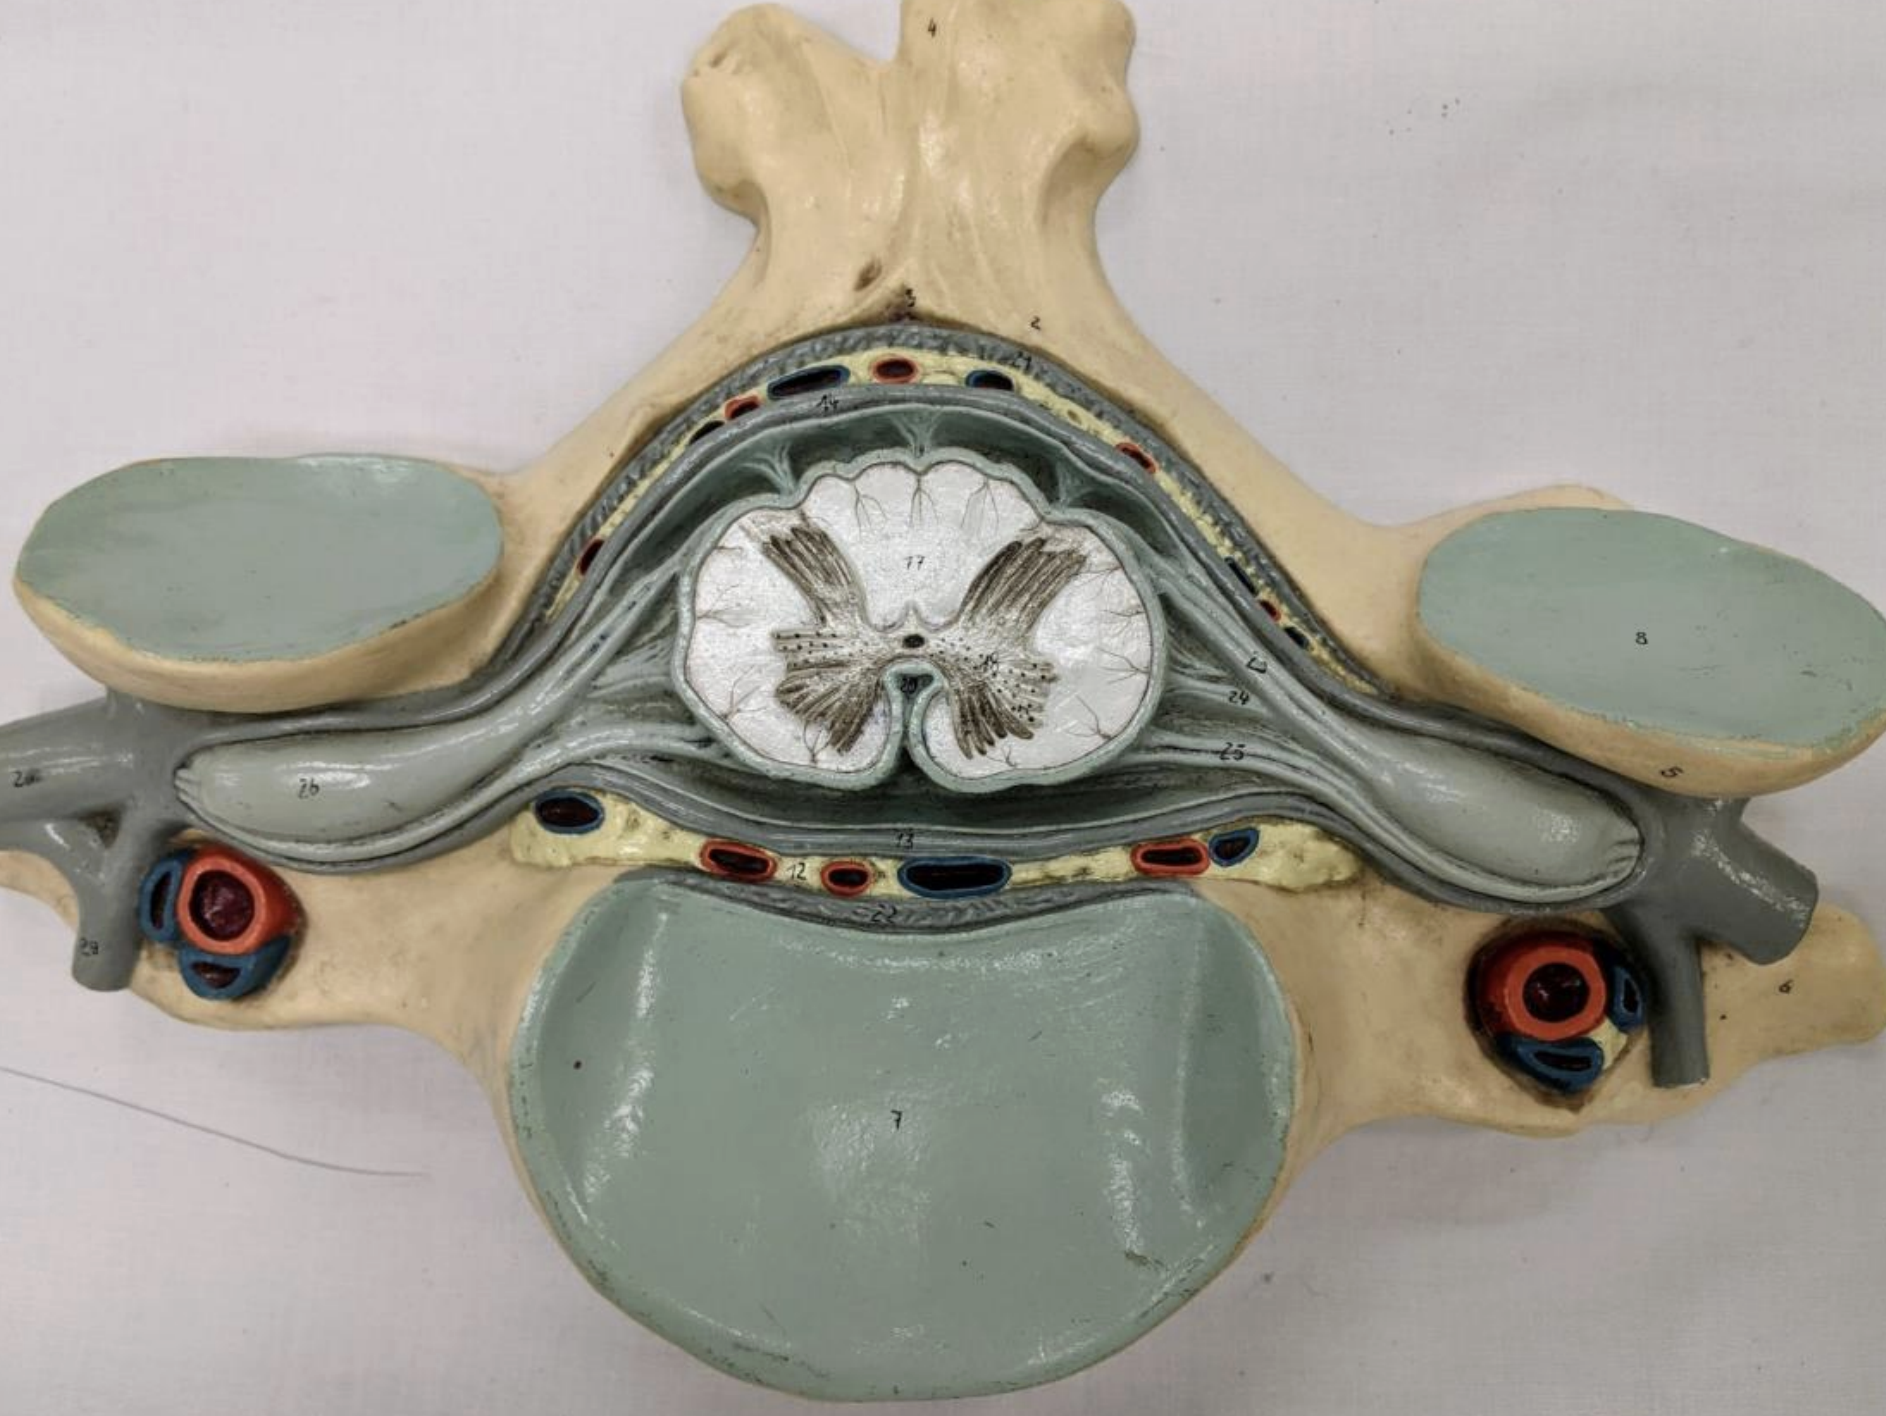

3 meninges:

Dura mater

Arachnoid mater

Pia mater

Epidural

Subarachnoid spaces